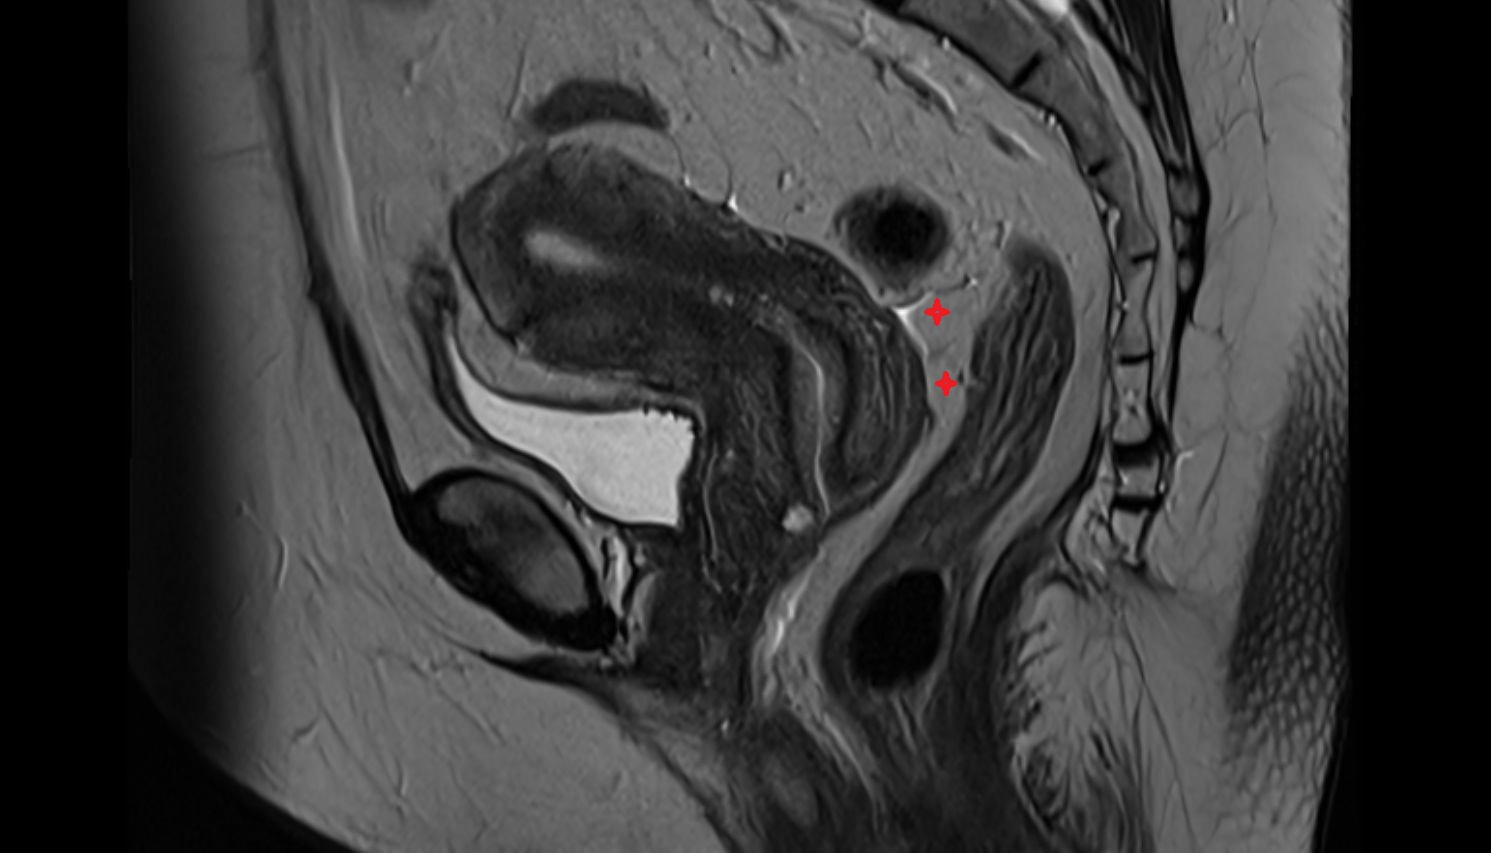

- Uterus

- Body of uterus

- Cervix of uterus

- Isthmus of uterus

- Vagina

- Fornix of the vagina

- Endometrium of uterus

- Myometrium of uterus

- Junctional zone of uterus

- Endocervical canal

- Stroma of the cervix

- Internal os of the cervix

- External os of the cervix

- Vesicouterine pouch

- Rectouterine pouch (pouch of Douglas)